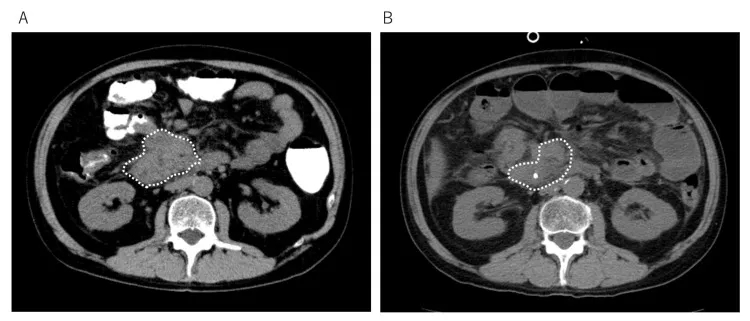

治疗效果显著:治疗前后3个月的腹部CT显示小肠癌病灶大幅减少(详见下图);血液检查提示CA19-9肿瘤标志物水平显著下降,胆红素降低,肝功能明显改善。更令人振奋的是,患者腹痛缓解,恢复流质饮食,PS评分提升至2分——无需拐杖即可步行至医院,且能自主完成如厕、洗澡等日常活动。

该案例证实,放疗与树突状细胞疫苗的联合方案可有效抑制癌症进展,为化疗无应答的晚期患者带来生存希望。尤其值得关注的是,WT1-DC与α-Galcer-DC的双疫苗组合,其协同激发的抗肿瘤免疫效应或优于单一疗法,为晚期癌症的免疫联合治疗带来了新的选择!

▼该患者接受DC免疫治疗前与治疗后的肿瘤大小对比

▲图源“Cureus”,版权归作者所有,如无意中侵犯了知识产权,请联系我们删除